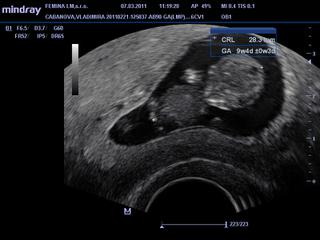

ahojte, ale ste sa rozpisali, nemala som vas ani kedy citat, ale nakoniec som to zvladla...gratulujem tie co mate uz tehu knizku....je mi luto, ze klajosa prisla o miminko....dnes som bola u lekara, vsetko ok, tak sa tesim, malinke sa poriadne hybalo...zakazdym mi da videa a fotky miminka, tak doma mame vecer kino 🙂 ...dnes som podla menzesu 9tt+6 a co ma sokovalo, lekar videl a ja takisto, ze to bude chlapcek, no uvidime ci sa to potvrdi - ma novy ultravuk...o tyzden znova kontrola, vraj vtedy bude najlepsie vidno, lebo neskor je male velke a uz nie je dobre vidno...28.3. idem na vysetrenia, odbery krvi, cize predpokladam, ze dostanem aj tehu knizku...to budem 13tt, skor nerobi ani odbery ani nedava knizku...ale zaklad, ze sme v poriadku...drzkam vam vsetkym palceky, nech sa mate ok a boli ste zdravucke 🙂

@lea1333 no bola som v soku, ked mi povedal, ze uz vidi nieco a hned nato vyzera to na chlapca a ja som to tiez videla....necakala som to tak skoro, myslela som, ze az niekedy v 20tt mi to povie....inac ani sa nespytal ci chcem vediet, ale tak uvidim ci sa mu to potvrdi, lebo my by sme chceli o trosku viac dievcatko, ale hlavne aby bolo zdravucke...ja som podla menzesu 9tt+6, podla ovulacie 9tt+5...babo zodpoveda datumu ovulacie, velkost akurat